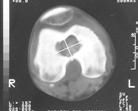

BT; kemik periostundaki değişiklikleri, kortikal değişiklikleri, kitle içindeki kalsifikasyon ve patolojik kırıkları gösterebilir.

MRI ise kemik medullasındaki tutulumu, yumuşak doku komponentini, damar sinir ilişkisini, eklem tutulumunu ve skip metastazı en iyi gösteren görüntüleme yöntemidir.

Klasik osteosarkom uzun kemiklerde kötü sınırlı, kemik yıkımına neden olan litik/sklerotik görünümlü lezyonlardır. Periostta kemiğe dik açıda oluşan kemik oluşumu (batan güneş manzarası) patogonomiktir. Yumuşak doku komponenti eşlik eder. BT kemik içerisindeki patolojileri göstermede yeterlidir. MRI ise yumuşak doku yayılımını, damar ve sinirin tutulup tutulmadığını, fiz hattının (büyüme kıkırdağı) etkilenip etkilenmediğini, komşu eklemin tutulup tutulmadığını, skip metastazların olup olmadığını ve uygun biyopsi yerinin belirlenmesinde yardımcıdır.